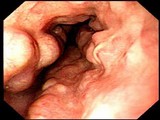

食管憩室

十二指肠球部溃疡

结肠癌

腺瘤

食管静脉曲张

食管炎

溃疡性结肠炎

锯齿状腺瘤

管状腺管腺瘤

小肠绒毛及淋巴滤胞

小肠绒毛

绒毛状腺瘤

肠息肉

直肠癌

增生性息肉